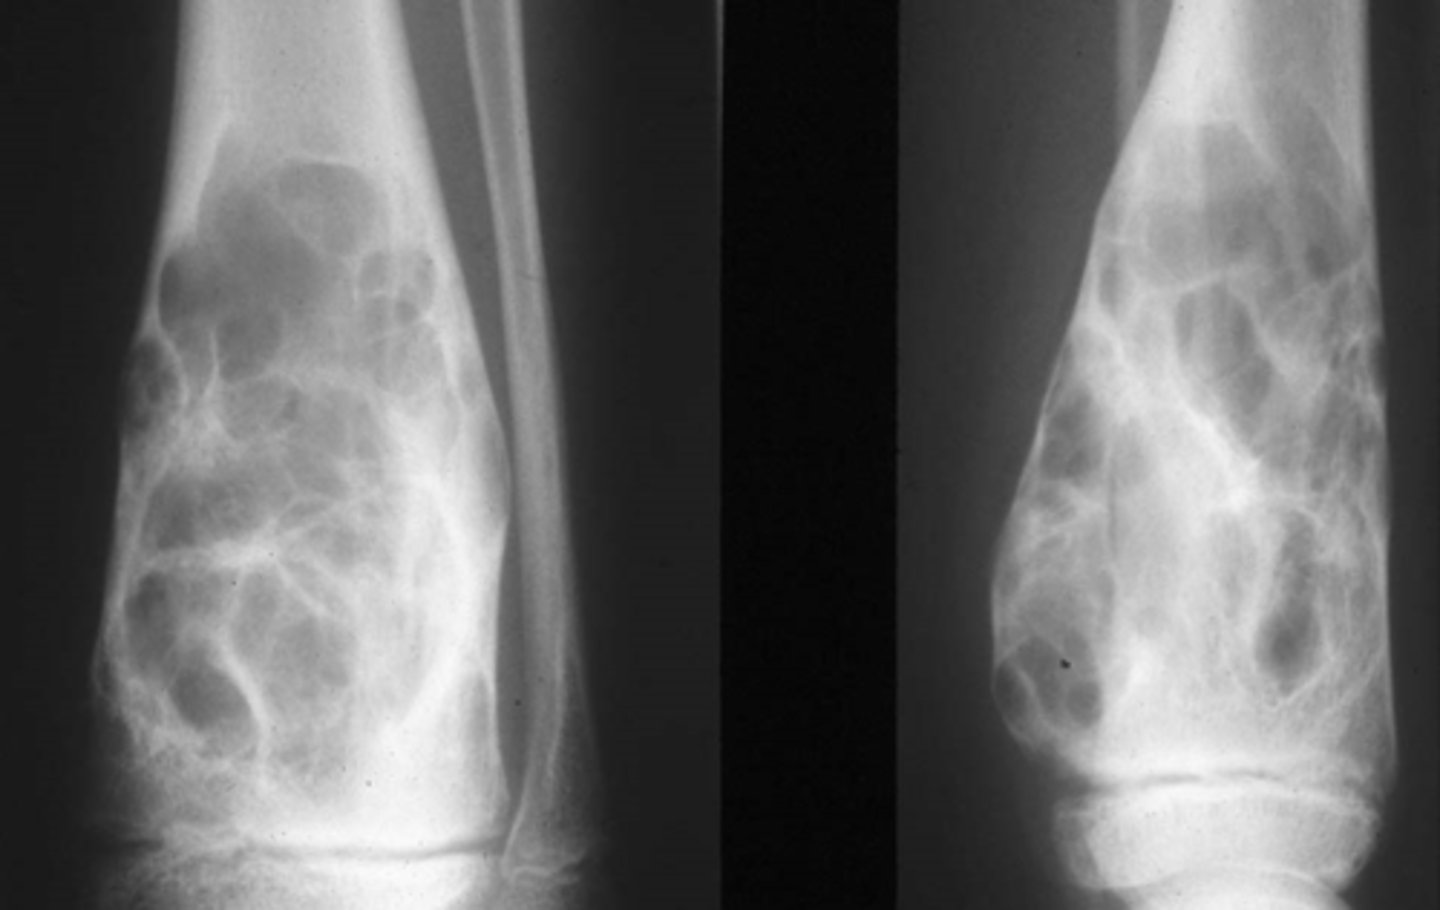

Chief Complaint: Mechanic presents with loss of grip strength. The patient reported having swollen fingers that previous hurt but the pain went away.

Objective Findings: ROM in his hands are decreased, notable swelling of the tissue in his fingers

Diagnostic imaging: X-ray

1. List the differential diagnoses. (Choose 3)

a. Ollier’s

b. Fibrous dysplasia

c. Benign bone tumor

d. Hereditary multiple exostosis

e. Multiple enchondromas

f. Scleroderma

g. Gardener’s Syndrome (aka familial colorectal polyposis, an autosomal

dominant form of polyposis characterized by the presence of multiple

polyps in the colon together with tumors outside the colon)

Expansile lesion

Cortical thinning

Geographic lesion

Vignette # 10

Sex: Male

Age: 24

2. What else could be associated with this condition? (Choose 3)

a. CREST sign

b. Sessile appearance

c. Geographic lesion

d. Blister of bone appearance

e. Periostitis (inflammation of layer of CT that surrounds bone)

f. Cortical thinning

g. Subchondral cysts

h. Expansile lesion